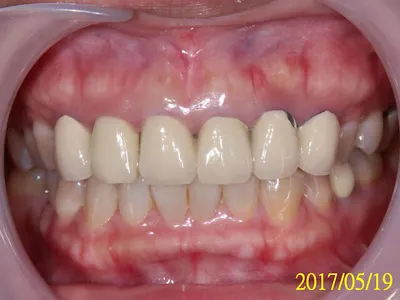

剛好這位臨床案例,算是大工程,我花了很長一段時間才搞定,正好可以說明這些FAQ。

黃小姐在大醫院從事醫療工作為知名醫療人員,有時需上節目,發現前牙區不好看,牙齦發黑、牙齒不美,急於求助於牙醫師希望改善牙齒狀況,以避免損及醫療專業形象。